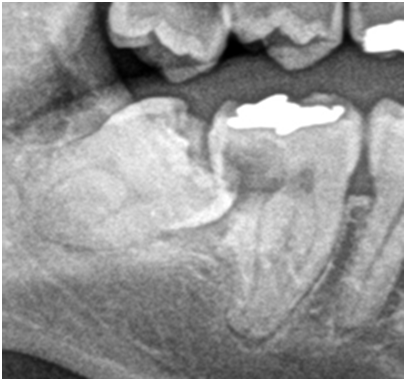

上の画像は、親知らずの手前の歯に黒い影ができているのが分かると思いますが、この黒い影がいわゆる虫歯です。親知らずが、隣の歯に衝突し清掃性が悪くなることで、こういった虫歯の原因になることがあります。